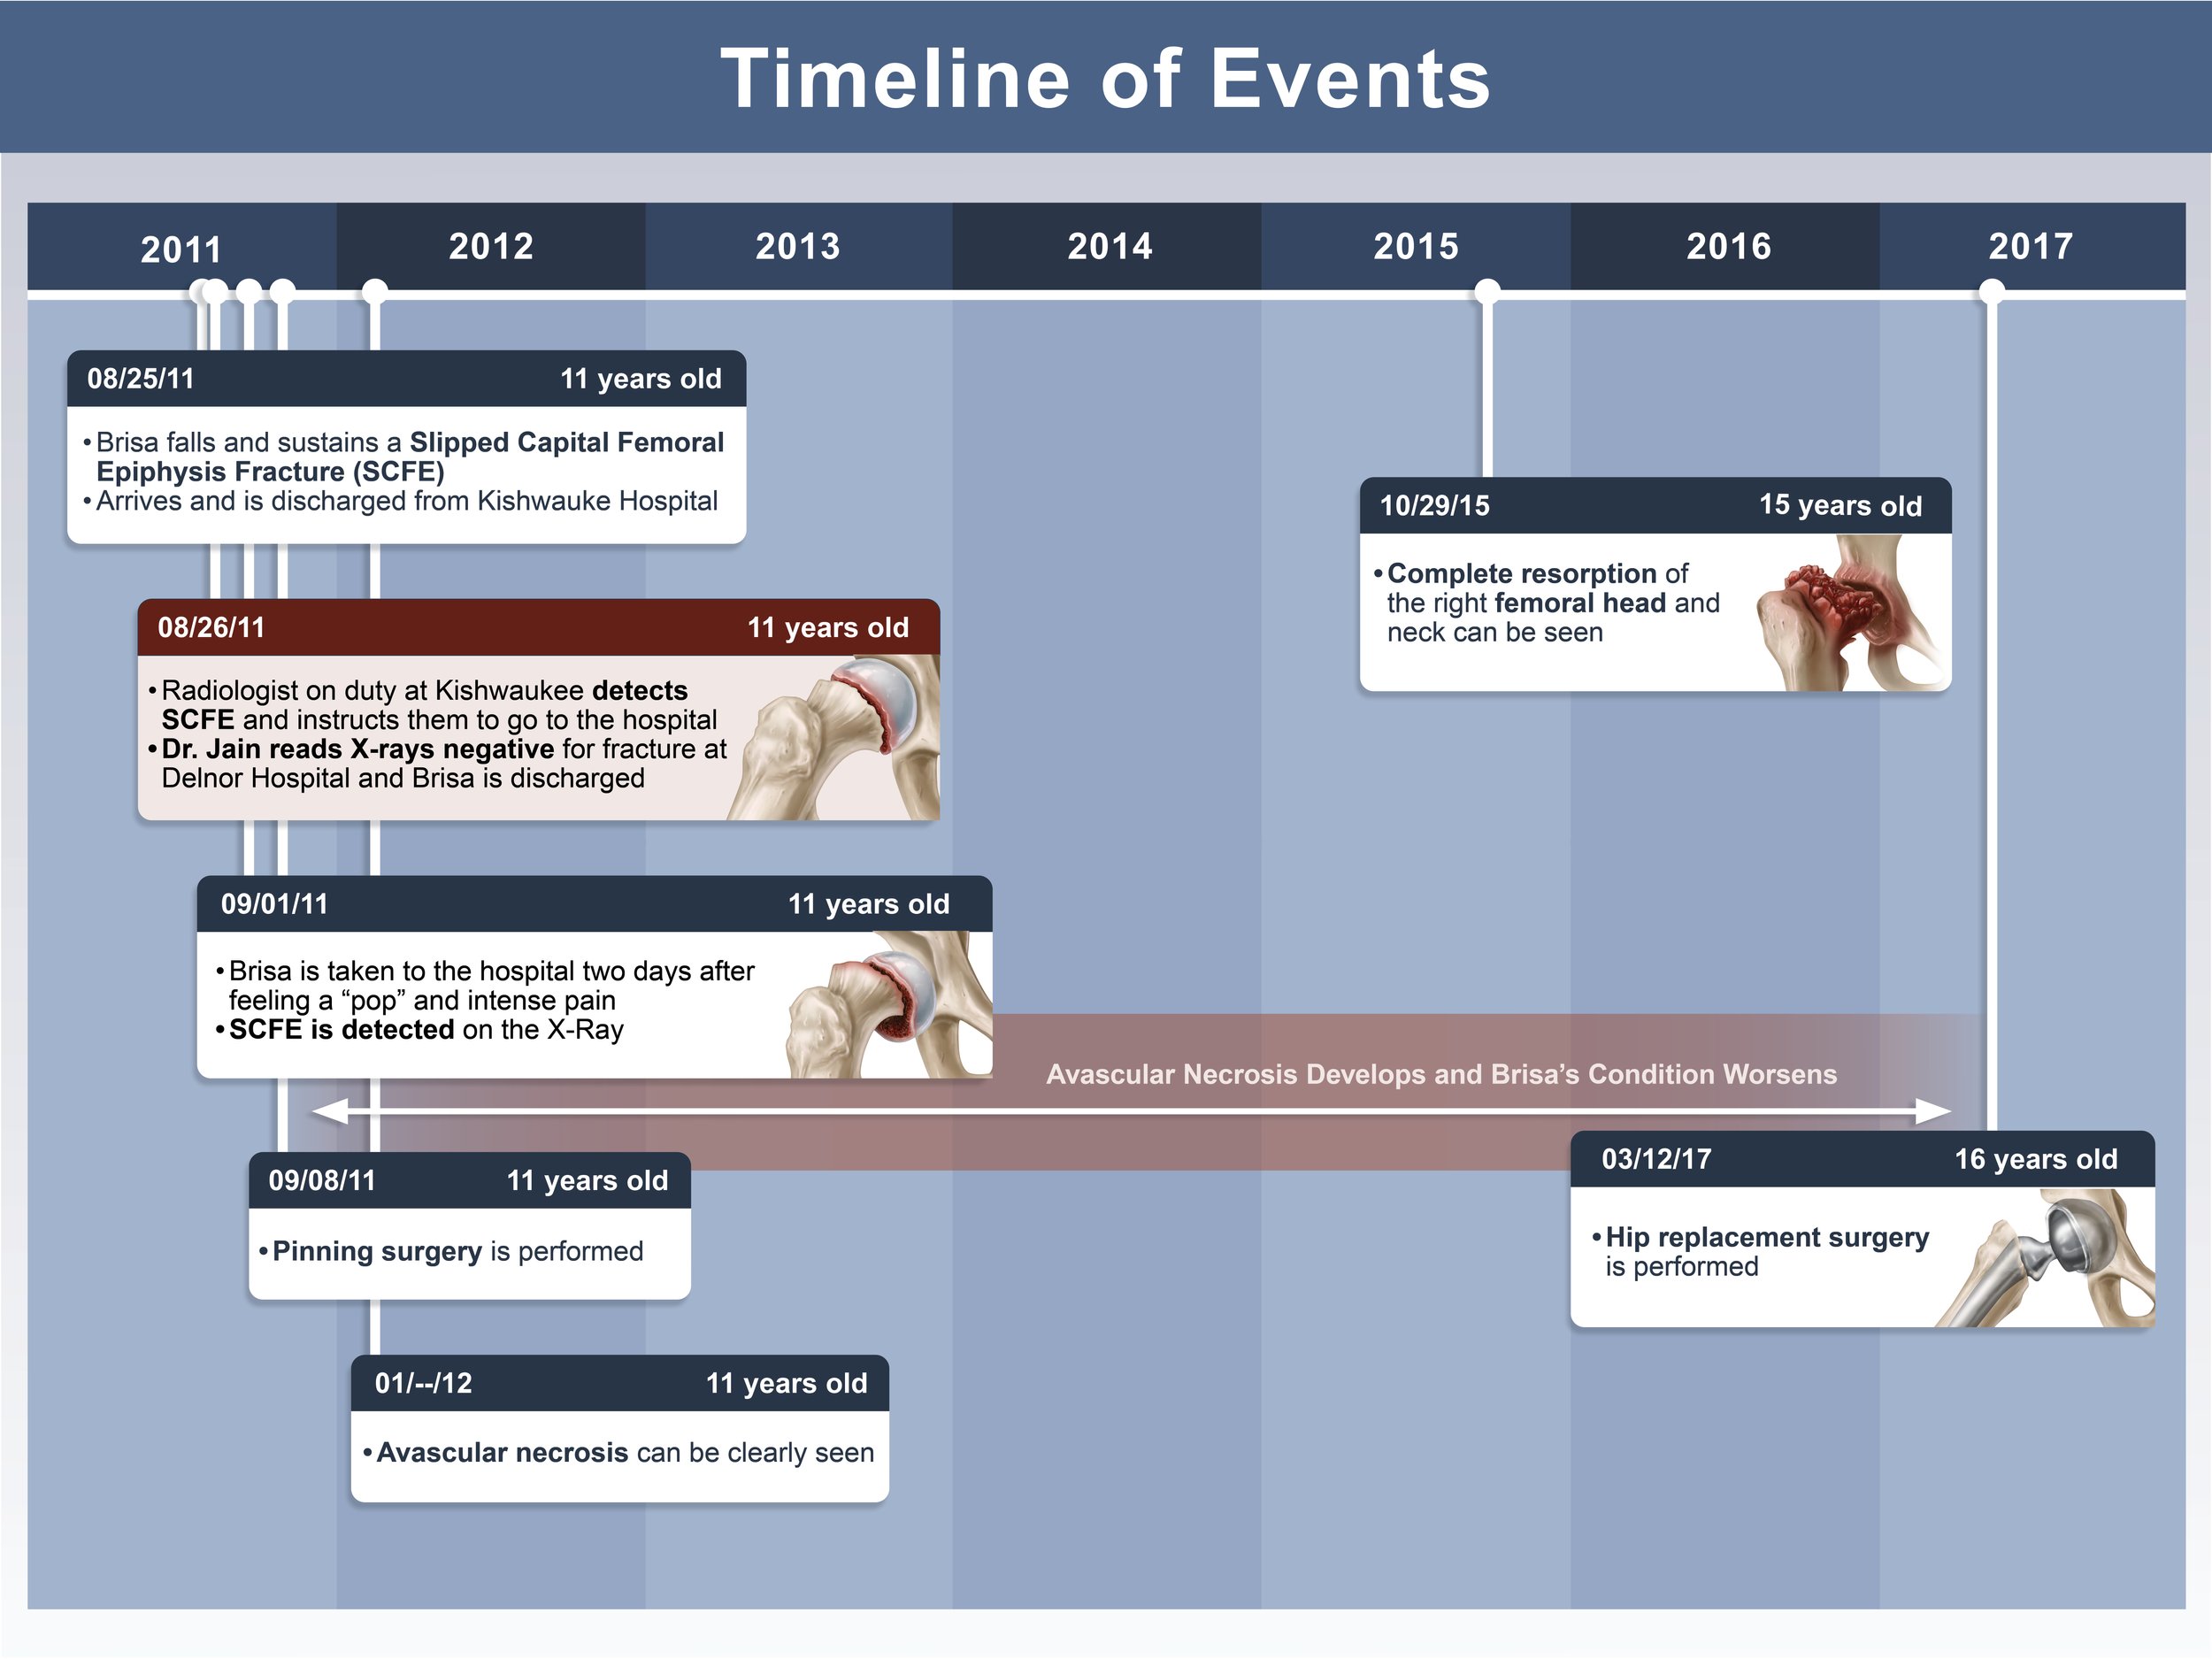

Medical Legal Illustration

Medical Illustration is important in the courtroom for many reasons including communicating scientific information for a lay audience, highlighting injury or anatomical differences, or simply representing potentially disturbing images in a more digestible way. Legal illustrations must be accurate, but still serve to help tell the defendant or plaintiff’s story.

SCFE Exhibit Design

These illustrated slides were created for a medical legal illustration course to accompany the plaintiff’s case in a “mock trial” presentation. The illustrations show the the progress of a slipped capital femoral epiphysis fracture (SCFE) that ultimately led to disability in a young girl. The illustrations were used to clearly communicate x-ray information to a lay audience and demonstrate why the doctor’s misread was easily avoidable. Additionally, the illustrations show the progression of symptoms as a result of that first missed diagnosis.

Adobe Photoshop, Indesign